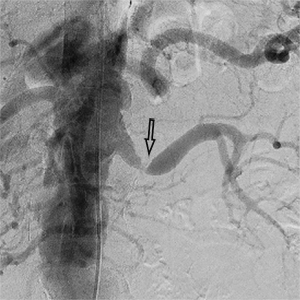

Ангіограми до та після стентування:

стеноз лівої ниркової артерії    балон, роздутий в зоні стенозу    відновлення отвору артерії

Субтотальний стеноз лівої

ниркової артерії

Балон-катетер зі стентом,

роздутий в зоні стенозу

Отвір артерії повністю відновлено